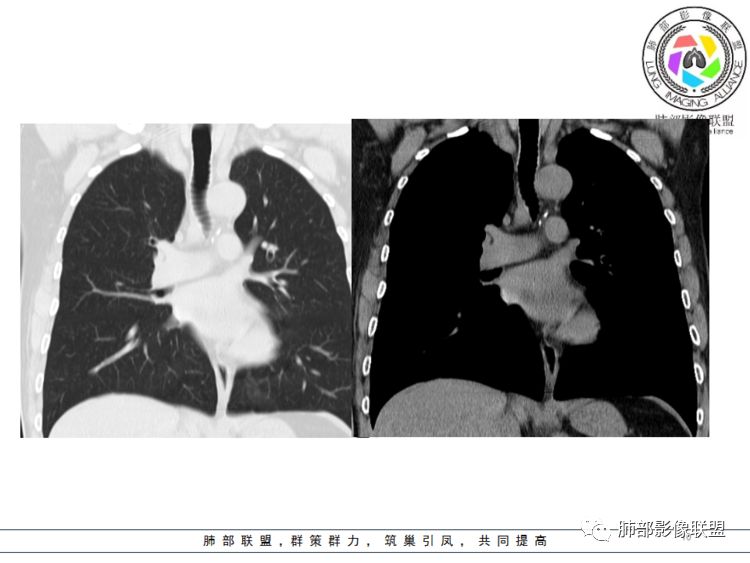

病灶跨气管壁内外,主体在外;边界清,密度均匀

明显看到气管壁软骨受压内移

局部是撑开的,就是说软骨不是破坏

表面隆起,有小斑点

无症状;倾向于良性,平滑肌瘤?神经源性肿瘤?不除外其他

南边分析:针对本例,病灶跨气管壁内外生长,常规跨内外的有:恶性肿瘤为主,其次就是神经源性、平滑肌瘤;常规的思维:跨内外就要看结构的变化气管的优势在于软骨相对密度高,而且成C型

我们如何分析这个病例?冠状位:软骨密度稍高;病灶区软骨部分区域不连续,外围连续,提示病灶推移为主,不是破坏为主;如果破坏,应该这些软骨显示不清,移位不明显

病灶从软骨见推移开,跨内外,因此定在良性。恶性是侵犯,破坏为主,如果破坏,应该这些软骨显示不清,移位不明显,不是推移为主这例病变定在良性,我们就要考虑:1、软骨之间的平滑肌来源;2、神经源性

病例小结      气管神经鞘瘤属于罕见的气管良性肿瘤,一般气管良性肿瘤或腔内或腔外生长的结节样改变,恶性肿瘤呈腔内外生长,但本例肿块向腔外生长,呈“冰山样改变”,即肿瘤的腔内部分较小而腔外部分较大,无周围组织侵犯。因此肿瘤腔内外生成不能作为鉴别气管良恶性肿块的绝对依据。        因此冠(矢)状位多平面观察、软骨是否破坏、气管壁有无增厚等细节观察,对于鉴别气管肿块良恶性有重要的参考性。

1.气管隆凸上右前壁不规则结节影,部分突入腔内,南边老师观察有推挤软骨环“破土而出”的形态特征。注意没有沿气管粘膜表面生长蔓延的生物学行为。

2.影像学病灶占据腔内外,但病灶边缘十分清楚。这点倾向良性。